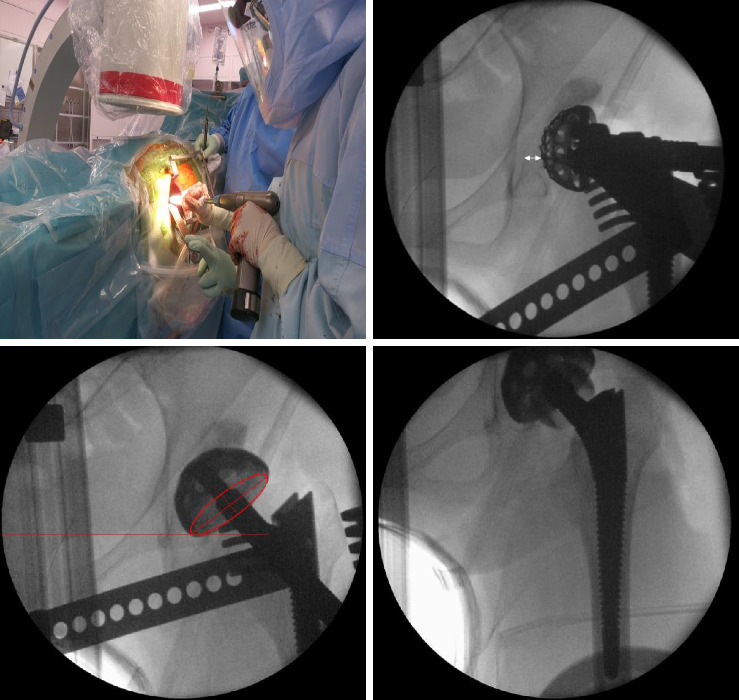

背景:充分的植入对于避免全髋关节置换术(THA)后的并发症是很重要的。本研究旨在评估在直接前路入路(DAA)中使用透视技术与在侧卧位(OCM)下使用单个种植体的前外侧入路相比,种植体放置的准确性和精确性。方法:我们回顾性地比较了DAA与透视和OCM中倾向评分匹配的tha。评估和比较各入路在Lewinnek杯安全区域的成成率、对齐的绝对差值和术前计划的定位。结果:两组均有33例患者符合本研究条件。DAA组在安全区内的杯子数量明显多于OCM组(33/33 vs. 25/33, p=0.0048)。DAA组与OCM组在靶杯倾斜度、前倾度和三维定位上的差异无显著性差异。茎对中无显著差异;然而,DAA组冠状排列方差的平等性较小(p=0.0047)。两组临床评分及并发症发生率无显著差异。结论:与OCM相比,透视下的DAA可提供更高的杯位精度和茎位精度。

Background: Adequate implantation is important to avoid complications following total hip arthroplasty (THA). This study aimed to evaluate the accuracy and precision of implant placement in the direct anterior approach (DAA) using fluoroscopy in comparison with the anterolateral approach in lateral decubitus position (OCM) using a single implant. Methods: We retrospectively compared propensity score-matched THAs in DAA with fluoroscopy and in OCM. The achievement ratio of the Lewinnek cup safe zone, absolute difference in alignment, and positioning from preoperative planning was evaluated and compared between each approach. Results: 33 patients in both groups were eligible for this study. Significantly more cups were inside the safe zone in the DAA group than in the OCM group (33/33 vs. 25/33, p=0.0048). No significant differences were found between the DAA group and OCM group regarding the discrepancy from the target cup inclination, anteversion, and three-dimensional positioning. No significant difference was noted in stem alignment; however, the equality of coronal alignment variances was smaller in the DAA group (p=0.0047). No significant differences were found in the clinical score and complication rate. Conclusion: The DAA using fluoroscopy may provide more accuracy for cup placement and precision for stem placement than OCM.